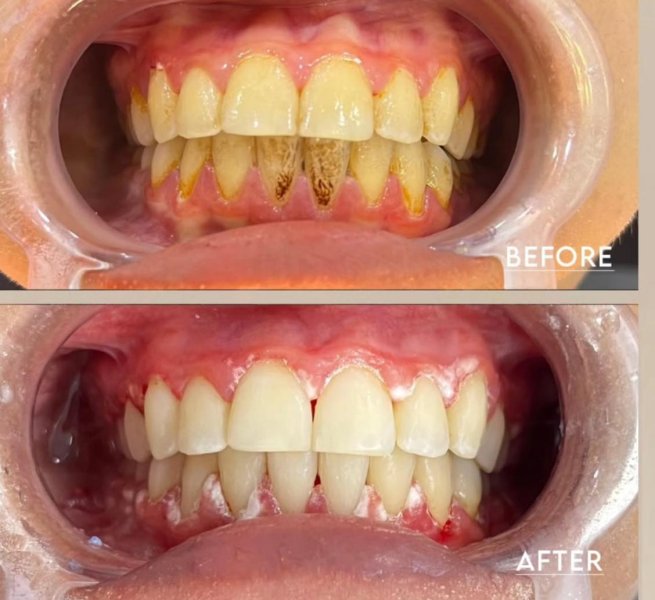

Dental Treatment Before and AfterClick To Enlarge White Teeth Lips Closeup Teeth Whitening Before After Teeth Whitening Transformation Before After Teeth Transformation Before After Man White Teeth Mustache Smile Teeth Whitening Transformation Before After Teeth Before After Transformation Teeth Before After Treatment Teeth Before After Composite Bonding Teeth Whitening Transformation Before After dental treatment dental treatment dental treatment dental treatment dental treatment dental treatment dental treatment dental treatment dental treatment dental treatment dental treatment dental treatment dental treatment dental treatment dental treatment dental treatment dental treatment dental treatment dental treatment